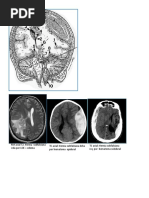

IMAGEN POR DIFUSION DE PROTONES

- basada en la detección aleatoria del movimiento

de los protones del agua

- el T2 no puede detectar los tipo de edema

- La IDP distingue entre edema vasogénico y

citotóxico

IMAGEN POR DIFUSION

- El edema citotóxico disminuye la difusión y el

ADC

- la sangre aguda impide la movilidad del agua por

su alta viscosidad

-los hematíes intactos y los coágulos también

afectan la difusión.

IDP

- en la secuencia por difusión se observa

hiperintensa

- el ADC se encuentra disminuido

- las alteraciones se pueden verse hasta en más

de dos semanas

Espectroscopia por R.M.

- detecta las alteraciones neuroquímicas asociadas

a condiciones patológicas

- mide metabolitos sintetizados en las neuronas

- NAA, colina, creatina, lactato, mioinositol

- el NAA disminuido representa daño neuronal

- el marcador ideal para LAD es la tasa NAA/Cr

Espectroscopia

- el nivel del NAA en la LAD se encuentra bajo al

igual que el NAA/Cr

- la depleción del NAA debido a LAD puede ser

responsable de los trastornos cognoscitivos

- en la LAD la colina se encuentra aumentada

pero es un marcador no específico

ERM

Lesión Características

LAD disminución del NAA y

NAA/Cr